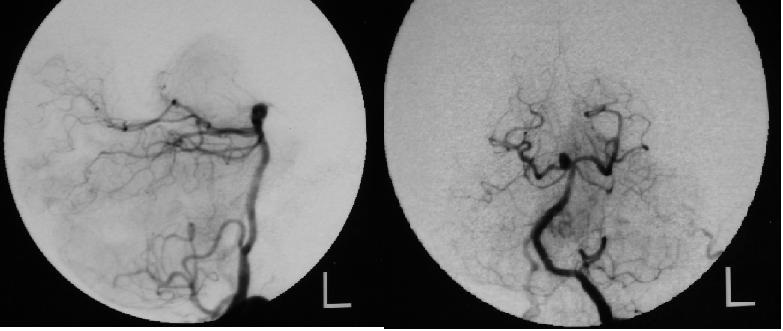

Wskaż prawdziwe twierdzenia dotyczące patologii znajdującej się na zdjęciach:

1) jest to najczęstsza lokalizacja tętniaków w tylnej części koła tętniczego;

2) na zdjęciach przedstawiono prawidłowy obraz naczyń mózgowych;

3) patologia przedstawiona na zdjęciach ze względu na swoje położenie nie może być leczona metodą wewnątrznaczyniową;

4) patologia przedstawiona na zdjęciach najczęściej manifestuje się poprzez krwawienie podpajeczynówkowe;

5) zdjęcia przedstawiają malformację tętniczo-żylną tylnej części koła tętniczego mózgu.

Prawidłowa odpowiedź to: